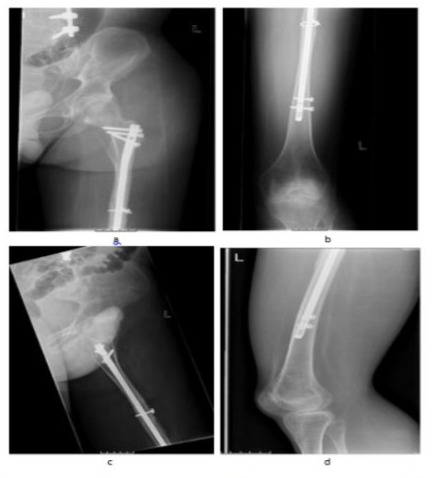

The patient was placed on a radiolucent table in supine position without traction. The operation was performed under spinal anesthesia. The dislocated proximal wedge fragment measured 7 x 1cm. We decided to fix this by means of a cable cerclage (Cable System, DePuySynthes, Oberdorf, Switzerland) in a minimal invasive technique without stripping the periosteum. A non-displaced wedge fragment was also fixed by means of a cable cerclage. Special attention was paid to bringing the nail in the exact longitudinal axis of the femoral shaft.Intraoperative fluoroscopy showed anatomic reduction and stable fixation (Figure 2a, b).

Figure 2a and b: Postoperative x-rays of the left femur showing anatomical alignment in a.p. (Figure. 2a) and lateral (Figure 2b) views.